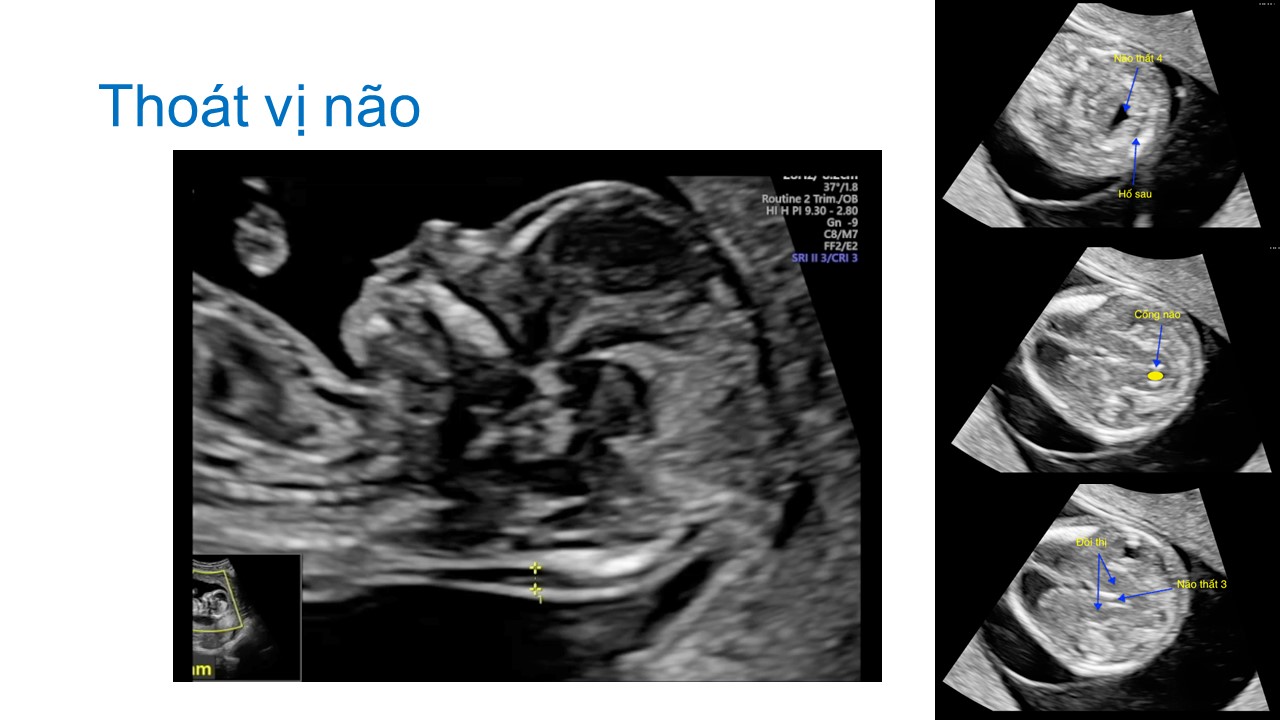

Siêu âm hình thai học quý I